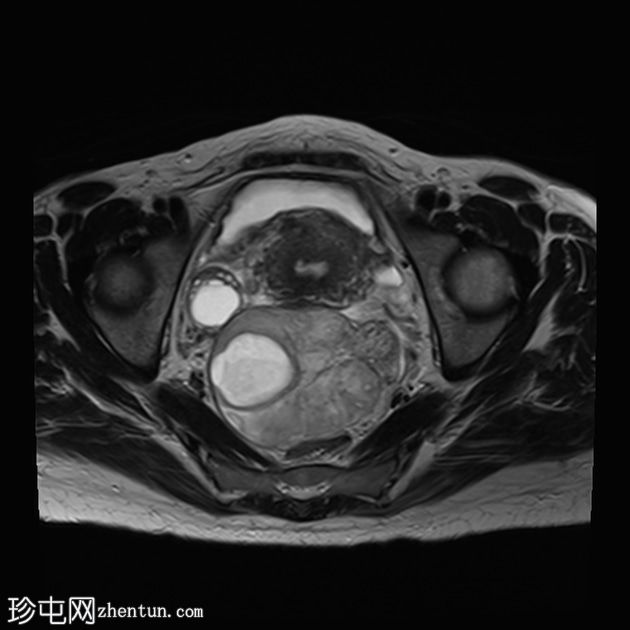

矢状位

T2加权像

左侧卵巢增大、水肿,位置异常,卵泡呈周边排列

左侧卵巢血管扭转,呈漩涡征

左侧卵巢实质出血性改变

上述左侧卵巢增大、水肿、位置异常、卵泡呈周边排列、实质出血的特征提示卵巢扭转伴出血。梗死。

患者被转诊至妇科医生处,并紧急行输卵管卵巢切除术。病理检查显示广泛的出血性梗死,卵巢包膜下仅残留薄薄一层完整组织。未发现恶性肿瘤